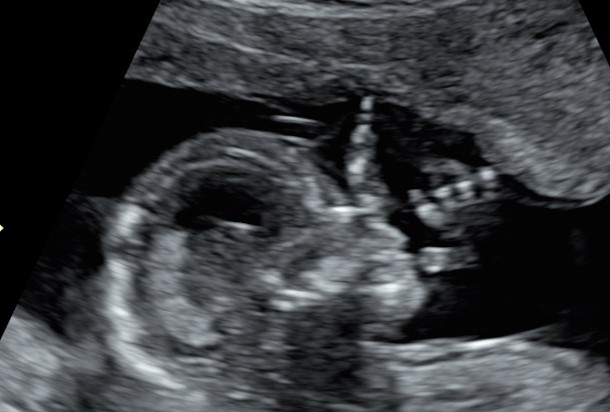

Siamo arrivati al quarto mese. Le incertezze, precauzione e scaramanzie dei mesi precedenti, stanno lasciando il passo a consapevolezza e gioia. L’espressione tipica dei genitori quando guardano il loro “tesoro” a queste settimane è “non pensavo che si vedessero così tante cose e che fosse già così bambino”. Infatti l’impressione ricevuta a queste settimane è di un tesorino alto 14-16 cm e del peso di poco più di 100-180 g, con tutte le sue cosine a loro giusto posto.

A questa epoca è possibile condurre un esame che impropriamente viene definito pre-morfologico, che ci permette di valutare le strutture principali, il tanto da poter affrontare con tranquillità il fondamentale appuntamento con l’ecografia morfologica del V mese.